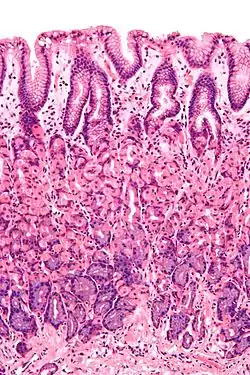

![]() Histological section taken from the gastric antrum, showing the mucosa of the stomach | |

The mucosa is composed of one or more layers of epithelial cells that secrete mucus, and an underlying lamina propria of loose connective tissue.[1] The type of cells and type of mucus secreted vary from organ to organ and each can differ along a given tract.[2][3]